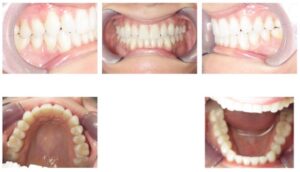

Case 4 – 14 attachments

Previous brand with typical attachment protocol (14 attachments, progress photos at 21 months)